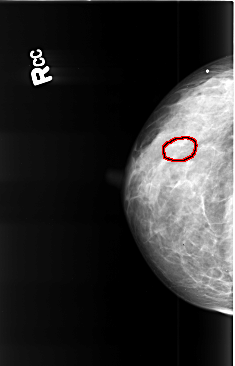

B_3422_1.RIGHT_CC

RIGHT_CC LINES 4384 PIXELS_PER_LINE 2816 BITS_PER_PIXEL 12 RESOLUTION 50 OVERLAY

FILE: B_3422_1.RIGHT_CC.OVERLAY

TOTAL_ABNORMALITIES 1

ABNORMALITY 1

LESION_TYPE CALCIFICATION TYPE PLEOMORPHIC DISTRIBUTION CLUSTERED

ASSESSMENT 4

SUBTLETY 3

PATHOLOGY BENIGN

TOTAL_OUTLINES 1

BOUNDARY